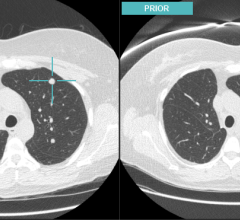

Blackford Analysis, a provider of software products that accelerate comparison of medical images, introduced its products to the Middle Eastern market at the Arab Health Congress 2014 in Dubai. Designed to be integrated directly into any image viewer, such as a PACS, Advanced Visualization Viewer or Universal Viewer, Blackford Analysis’ products work within existing systems to enable instant comparison of multiple image studies.